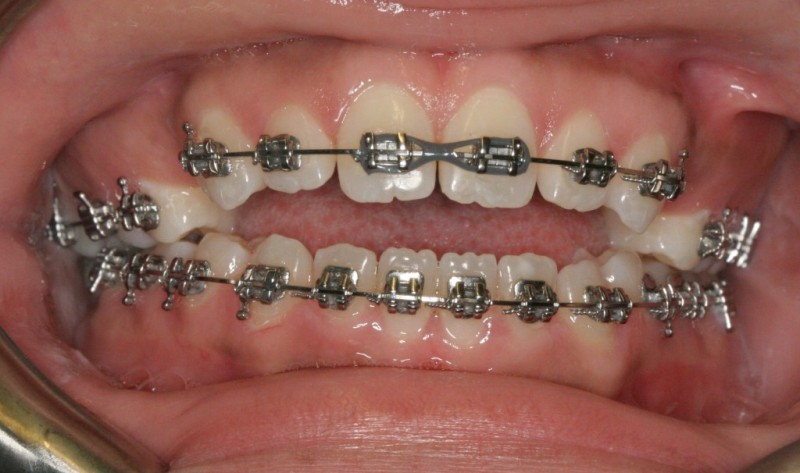

After Orthodontic Setup - Presurgical